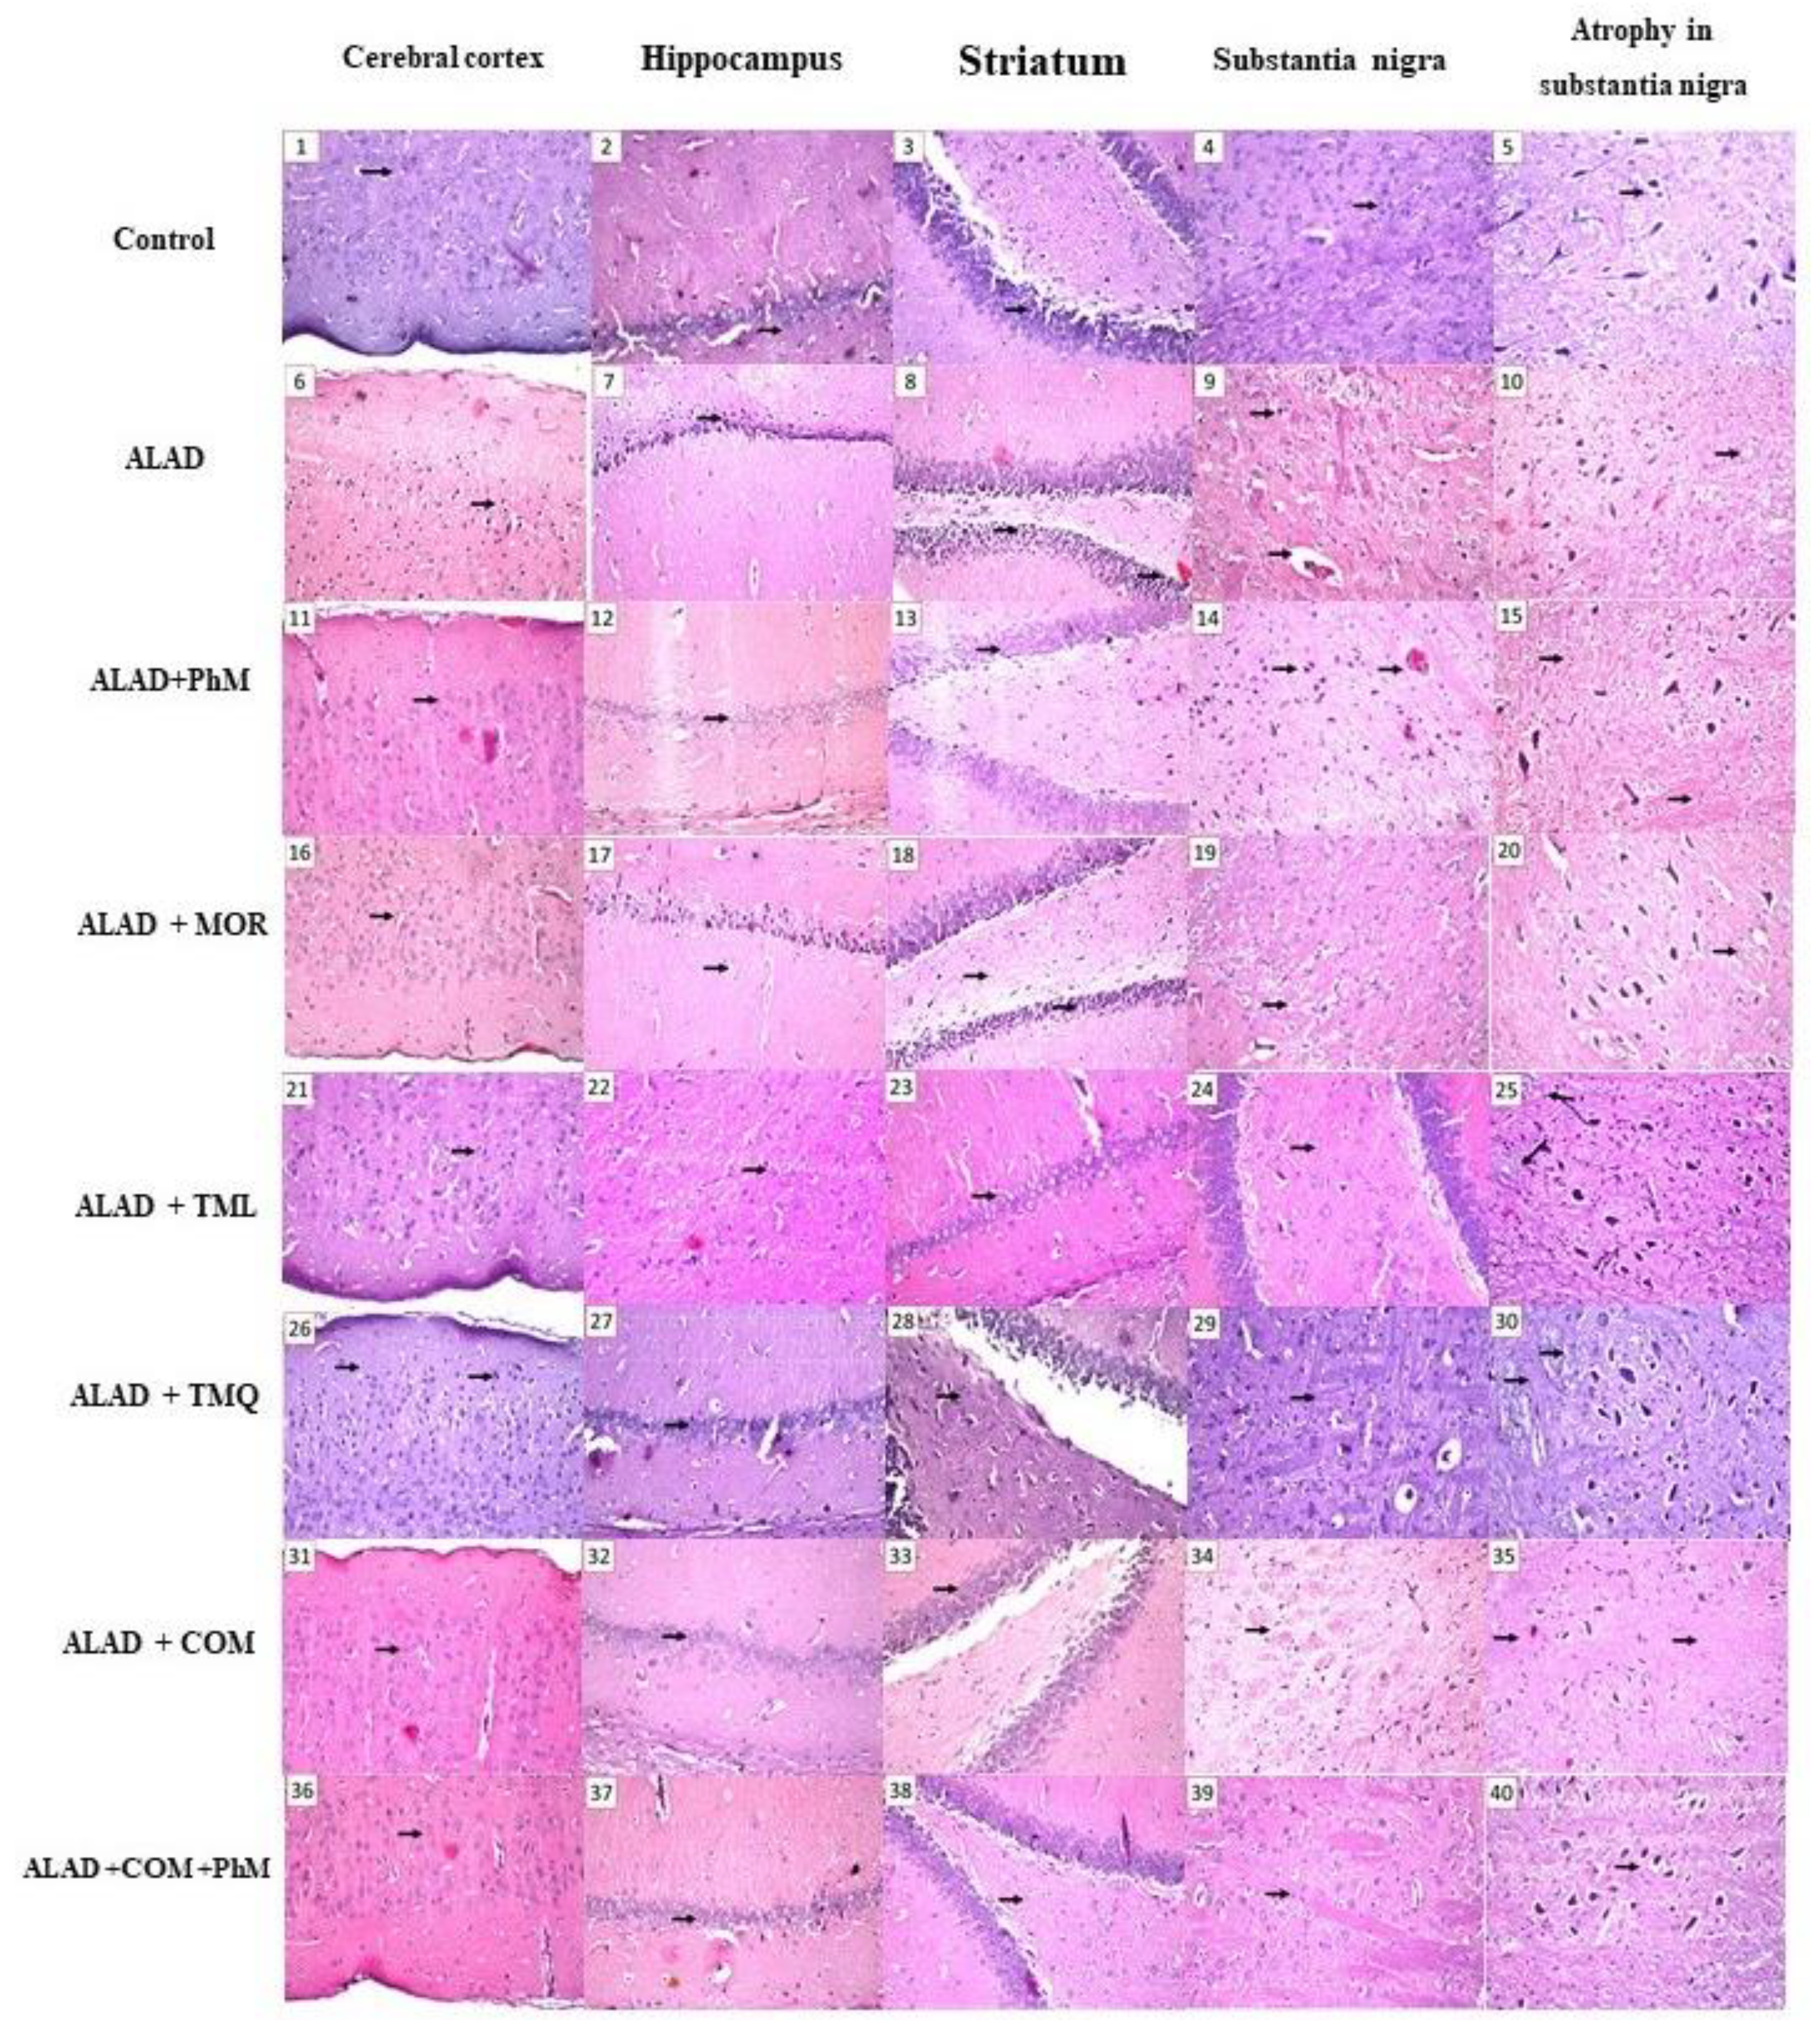

2.2. Histopathological Evaluation of Brain Tissues

| Nuclear pyknosis and degeneration | Cerebral cortex | - | +++ | - | - | ++ | + | - | - |

| The subiculum and fascia dentate of the hippocampus | - | +++ | - | ++ | - | - | - | - | |

| Focal eosinophilic plagues in the striatum | - | +++ | +++ | + | + | - | + | - | |

| Atrophy in the neuronal cells of the substantia nigra | - | +++ | +++ | + | - | + | + | - | |